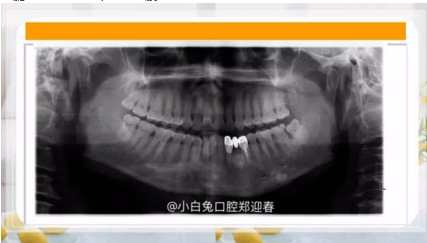

干脆潛到海底深處,猶如一艘核潛艇!

3.png